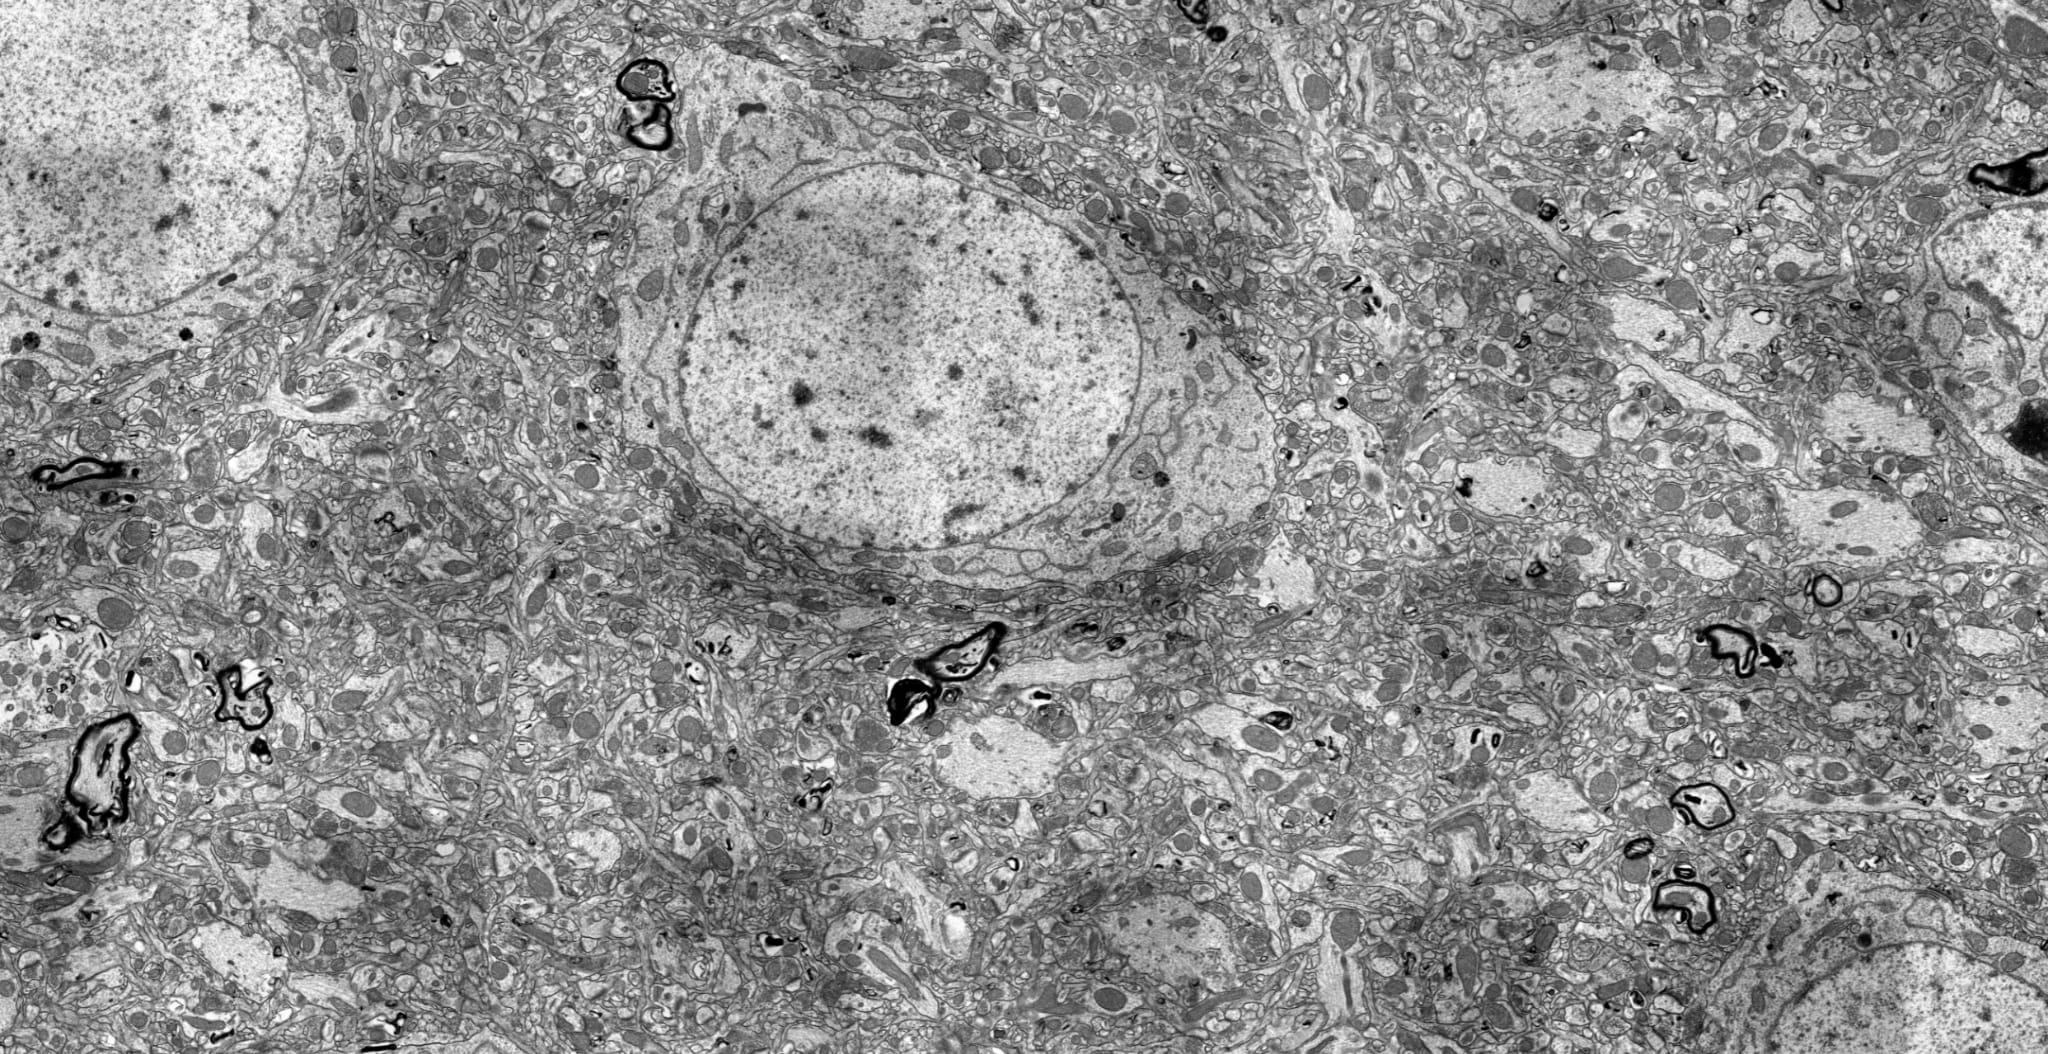

People are rushing to build bigger and bigger single cell foundation models (trained on RNA sequencing data), but in my view we have not extracted even a small fraction of the knowledge and capabilities that already exist inside the models we have today.

To explain what I mean, I want to argue three things in this post, and then show the empirical work behind them.

Thesis 1: Biological foundation models are not like LLMs, and the field's habit of evaluating them the same way is causing us to systematically underestimate what they contain. When you interact with GPT, the surface-level outputs (the text it generates) are a fairly good proxy for the model's capabilities. You can read what it writes and form a reasonable opinion. Biological foundation models are fundamentally different in this respect. A model like Geneformer or scGPT takes a cell's gene expression profile and produces embeddings, predictions of masked genes, or cell type classifications. These surface-level outputs are only a small sliver of what the model is doing internally. The model has been trained on tens of millions of cells, and the representations it has built to solve its training objective contain compressed biological knowledge that never directly appears in any output you can look at. Evaluating these models by their benchmark performance on cell type annotation or perturbation prediction is like evaluating a human scientist by asking them to fill in blanks on a multiple-choice exam.

Thesis 2: People keep calling biological foundation models "virtual cells," but this is a label that is implied rather than tested or validated. The term gets used in grant applications, press releases, and even some papers, as though it were an established fact that these models have internalized a working simulation of cellular biology. Maybe they have. Or maybe they have learned sophisticated statistical regularities that look like biology on the surface but dissolve under closer inspection. My work shows these models are, in a meaningfull sense, the models of the cells, but that is an empirical claim that needs empirical treatment.

Thesis 3: The right tools already exist, and they come from the AI safety community's work on mechanistic interpretability. Sparse autoencoders (SAEs), causal circuit tracing, feature ablation, activation patching: these methods were developed to understand language models, largely motivated by alignment concerns. It turns out they are extraordinarily well-suited to biological foundation models, and for a good reason: in language models, when you discover a circuit, you often lack ground truth about whether the circuit is "correct" in any deep sense, because there is no objective external reality that the model's internal computations are supposed to correspond to. In biological foundation models, you have decades of molecular biology, curated pathway databases, genome-scale perturbation screens, and well-characterized regulatory networks to validate against. Biology gives you the ground truth that language lacks. This makes biological FMs arguably the best (real) testbed for mechanistic interpretability methods that currently exists.

What follows is the story of three papers I recently produced, each building on the previous one, in which I applied the SAE-based interpretability toolkit to the two (not a long time ago) leading single-cell foundation models (Geneformer V2-316M and scGPT whole-human) and progressively mapped what they know, how they compute, and where their knowledge runs out.

The first question was very simple: what is inside these models?

Neural networks encode information in superposition. This is well-established in the interpretability literature for language models, but nobody had systematically demonstrated it for biological foundation models or attempted to resolve it.

I trained TopK sparse autoencoders on the residual stream activations of every layer of Geneformer V2-316M (18 layers, d=1152) and scGPT whole-human (12 layers, d=512). The SAEs decompose the dense, superimposed activations into sparse, interpretable features, each of which (ideally) corresponds to a single biological concept. The result was a pair of feature atlases: 82,525 features for Geneformer, 24,527 for scGPT, totaling over 107,000 features across 30 layers.

The superposition is massive. 99.8% of the features recovered by the SAEs are invisible to standard linear methods like SVD, meaning that if you tried to understand these models using PCA or similar approaches, you would be looking at 0.2% of the representational structure. This alone should give pause to anyone who thinks they understand what these models are doing based on standard dimensionality reduction.

The features are biologically rich. Systematic annotation against five major databases (Gene Ontology, KEGG, Reactome, STRING, and TRRUST) revealed that 29 to 59% of features map to known biological concepts, with an interesting U-shaped profile across layers: high annotation rates in early layers (capturing basic pathway membership), declining in middle layers (where the model appears to build more abstract, less easily labeled representations), and rising again in late layers (where it reconstructs output-relevant biological categories). The features also organize into co-activation modules (141 in Geneformer, 76 in scGPT), exhibit causal specificity (when you ablate one feature, the downstream effects are concentrated on specific output genes rather than diffusing broadly, with a median specificity of 2.36x), and form cross-layer information highways connecting 63 to 99.8% of features into functional pipelines.

So far, so encouraging. The models have clearly internalized a great deal of organized biological knowledge: pathways, protein interactions, functional modules, hierarchical abstraction. This looks close to the "virtual cell" story that the field likes to tell.